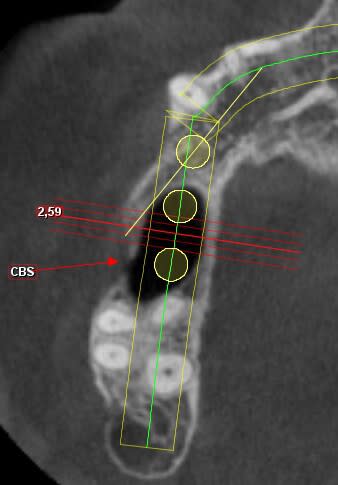

d'abord, je ne te conseille pas de faire ton sinus par voie latérale mais d'utiliser la cbs comme fenêtre d’accès.

voici juste pour commencer la présentation du cas..

50 ans, fumeuse, belle femme, CBS suite à une malheureuse extraction

fermeture de la cbs par un chir maxillo-faciale à l'aide de la boule de Bichat

6 ans plus tard elle se plaint de gênes à ce niveau.

elle veut des dents.